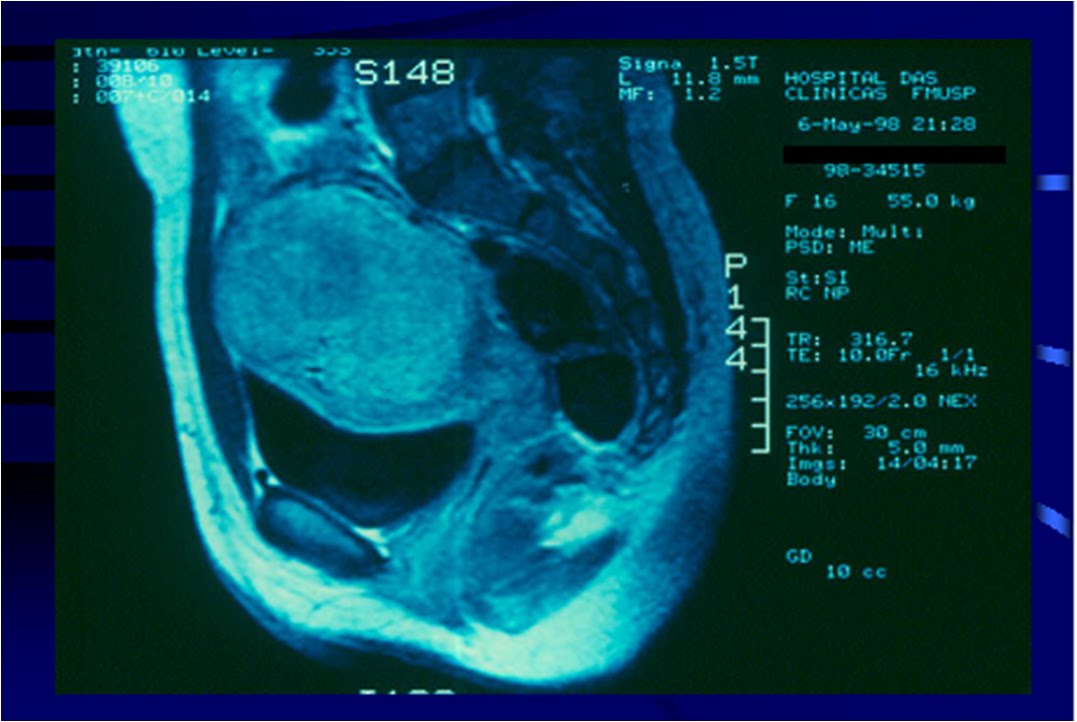

Ressonância Magnética

A ressonância magnética é um exame em que se obtém imagens espaciais mais precisas do corpo através de um equipamento complexo e caro que usa o princípio da vibração das moléculas dos órgãos do corpo quando submetidas a um campo magnético. Ele está indicado nos casos de mioma mais complexos em que existe necessidade de um estudo mais aprofundado e mais detalhes em relação ao número, volume e posição dos miomas. Geralmente a ressonância é necessária em úteros com volume acima de 400 cc (mais ou menos um peso de 400 gramas; nos casos em que existam mais de 4 miomas ou durante o lanejamento de alguns tratamentos mais complexos.

- Imagem de ressonância nuclear magnética de paciente com mioma uterino.